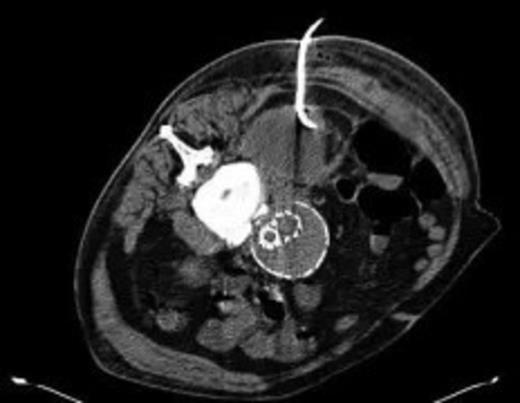

Four weeks following discharge the patient was re-admitted with feeling increasingly unwell, recurrent pyrexia, loss of appetite and mild shortness of breath on exertion. Physical examination was unremarkable except for a temperature of 38.3 centigrade. Blood tests on admission showed Hb 11.4 g/dl (11.5-16.0 g/dl), white cell count 13.1×109/L (4-9.2 x 109/L) and CRP 68mg/L (<3 mg/L). Contrast enhanced CT scan (Fig. 2,3) showed a 50 mm maximum retroperitoneal collection situated between the right kidney and the right iliac vessels. It contained a few loculi of gas. A diagnosis of postoperative right psoas abscess was made. The patient was started on intravenous broad spectrum antibiotics – Tazocin (Piperacillin+ Tazobactam) and Metronidazole. CT guided drainage was carried out using a 10 French gauge pigtail catheter locked pigtail (Meditech Flexima regular all-purpose drainage catheter sets with locking pigtail (Boston Scientific)) (Fig. 4). The isolation of E. coli from the collection with negative Hemocultures suggested a bowel source for the infection but no actual breach was demonstrable. The bowel surgeons ruled out colonic pathology.

A 50 mm maximum retroperitoneal collection situated between the right kidney and the right iliac vessels